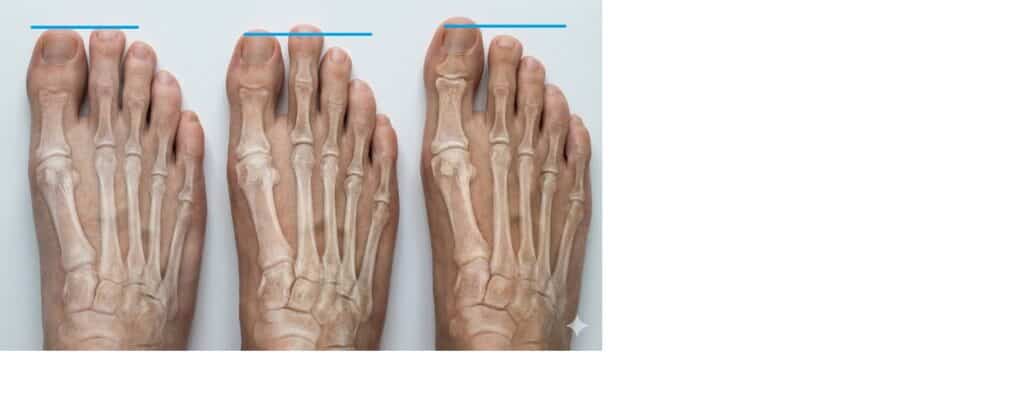

4. סיווג ודרגות חומרה של הלוקס ואלגוס: המדריך הקליני והרדיולוגי

מבוא: מעבר למראה העין

בעוד שמטופלים בוחנים את ההלוקס ואלגוס (Hallux Valgus – HV) לפי גודל ה"בליטה" (Bunion) החיצונית, העולם הרפואי מסתמך על מדידות זוויתיות מדויקות המבוצעות בצילום רנטגן בעמידה (Weight Bearing X-ray).

החשיבות של סיווג החומרה היא קריטית: היא זו שקובעת האם ניתן לטפל שמרנית, האם נדרש ניתוח, ואיזה סוג ניתוח בדיוק (חיתוך העצם בקצה או בבסיס).

כלי המדידה: הזוויות הקובעות

כדי לקבוע את הדרגה, אנו מודדים בעיקר שתי זוויות מרכזיות:

- זווית HVA (Hallux Valgus Angle):הזווית הנוצרת בין הציר הארוך של עצם המסרק הראשונה (1st Metatarsal) לבין הציר של הגליל המקורב בבוהן (Proximal Phalanx).

- נורמה: עד 15 מעלות

- זווית IMA (Intermetatarsal Angle):הזווית שבין עצם המסרק הראשונה לשנייה. זווית זו מלמדת אותנו כמה "רחוק" ברחה עצם המסרק פנימה (Varus).

- נורמה: 9 מעלות

חלוקה לדרגות חומרה

הספרות הרפואית (על פי Mann and Coughlin) מחלקת את הפתולוגיה לשלוש דרגות עיקריות:

סולמות ויזואליים (ללא רנטגן)

מכיוון שלא תמיד זמין רנטגן, פותח סולם מנצ'סטר (The Manchester Scale).

זהו כלי המציג 4 תמונות סטנדרטיות של כף רגל:

- No Deformity

- Mild

- Moderate

- Severe

מחקרים הראו מתאם (קורלציה) גבוה מאוד בין מה שהמטופל רואה בסולם מנצ'סטר לבין הזוויות בפועל ברנטגן. זהו כלי מצוין למטפלים פיזיים ופודיאטורים להערכה ראשונית.